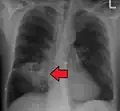

Description de cette image, également commentée ci-après

Tomodensitométrie (TDM) du thorax montrant une pneumonie bilatérale avec abcès, épanchements et cavernes. Homme de 37 ans.